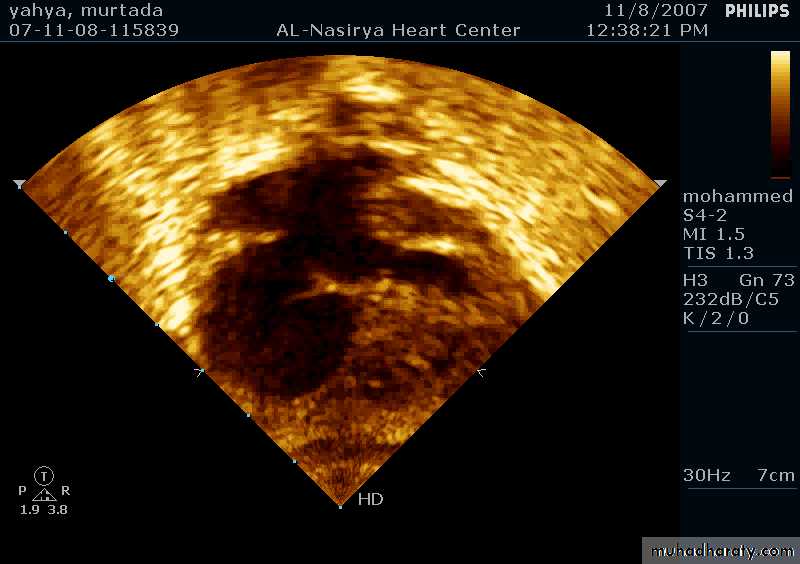

33Echocardiography & TEE

Shows the size of the defectThe direction of blood flow

The pulmonary artery pressure34

Ostium Secundum ASD

35